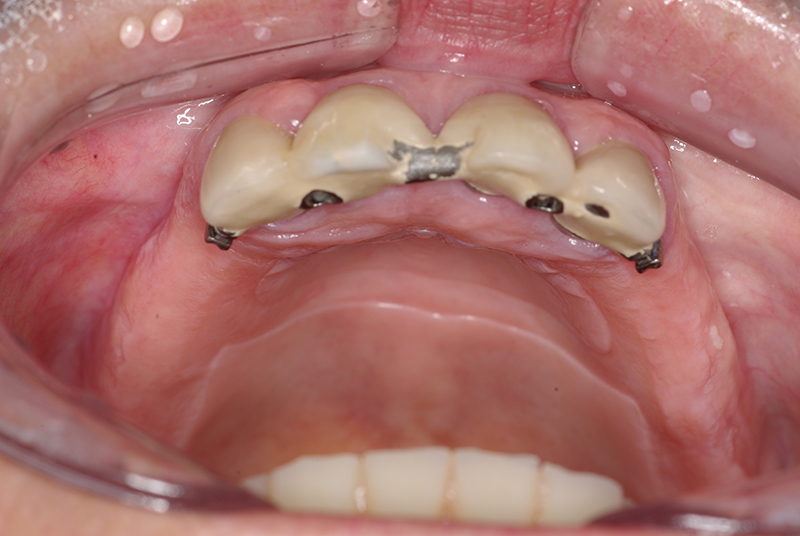

- Cirurgia de Instalação dos Implantes: Os implantes são fixados no osso maxilar ou mandibular, proporcionando uma base sólida para a prótese.

- Fixação da Prótese: Em até 72 horas após a cirurgia, a prótese provisória é instalada, permitindo que o paciente recupere a funcionalidade e a estética imediatamente.

- Conforto e Estética: A prótese provisória é funcional e visualmente semelhante aos dentes naturais.